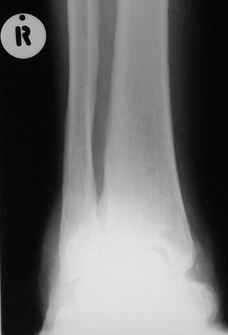

Кто шустрый - при какой патологии встречается так называемые "суставы Шарко"?Второе приобретение доктора Эмануэла мне понравилось своим романтическим названием: Candle bone - <кость-в-виде-оплывающей-свечи> : Просто редкая патология:

VR>Второе приобретение доктора Эмануэла мне понравилось своим романтическим названием: Candle bone - <кость-в-виде-оплывающей-свечи> : Просто редкая патология:

Мелореостоз

Под названием "мелореостоз" описано около 50 случаев врожденного заболевания скелета, выражающегося в совершенно

своеобразном одностороннем остеосклерозе костей одной только конечности. Можно не сомневаться в том, что

мелореостоз встречается далеко не редко; мы наблюдали свыше 20 случаев. Вполне естественно, что отдельные новые

казуистические наблюдения, не вносящие в науку никаких новых фактов и не возбуждающие новых мыслей и обобщений,

остаются неопубликованными.

Остеосклероз при этом заболевании захватывает не всю кость по окружности, а простирается слегка волнистой

полосой вдоль длинной оси конечности (рис. 223, К), переходя через линию суставов на другие кости. Таким образом,

может оказаться пораженной целая верхняя или нижняя конечность или больший или меньший ее периферический участок,

например, часть лопатки, полуцилиндр плечевой кости, часть цилиндра лучевой кости и скелет II пальца вместе с

лежащими по этой оси участками запястных костей или же часть - медиальная или латеральная - бедренной,

болынеберцовой кости с продолжением и расширением процесса на предплюсневые и плюсневые кости и соответствующие

по длиннику фаланги одного или нескольких, но никогда не всех пальцев. Описавшие эту болезнь в 1922 г. Жоани

(Joanny) и Лери (Leri) сравнивают остеосклеротические полосы с картиной, напоминающей стекающий со свечи и

застывающий стеарин или воск, отсюда и название "мелореостоз" - "стекающая вдоль конечности кость".